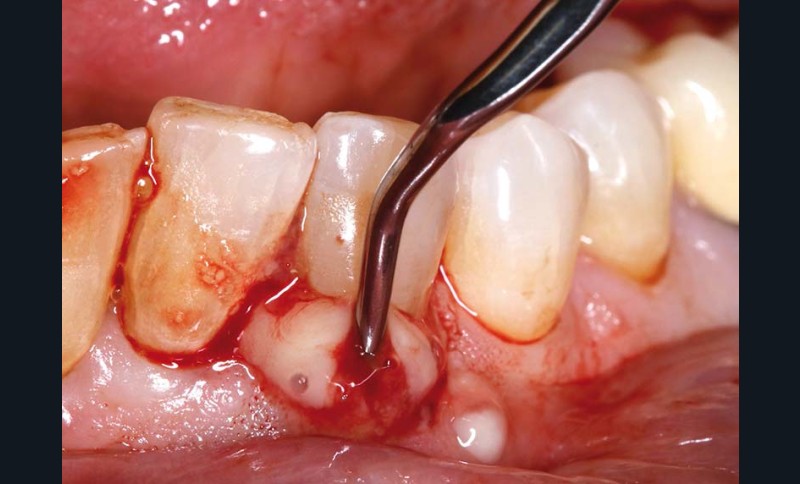

Cliniquement, la gencive présente un aspect tuméfié, rouge/violacé ; elle est lisse, brillante et à tendance hémorragique (fig. 1). Une suppuration, majoritairement par le sulcus, est observée de manière spontanée ou provoquée sous légère pression. La palpation et la percussion sont douloureuses. Une mobilité dentaire, variable selon l’atteinte desmodontale, peut être présente.

– par la poche parodontale par débridement (insert U.S et/ou curette de Gracey) (fig. 3),